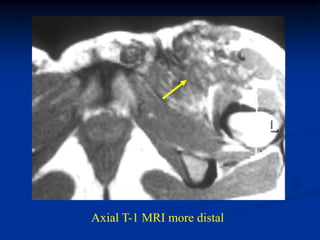

Case #314.1             Angiosarcoma Thigh

52 yr old male with

tender mass in proximal

anterior thigh area 3 mos

Axial T-1   STIR

Cor STIR   Sag STIR